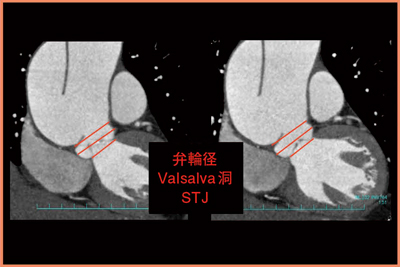

収縮期と拡張期で弁の状態を確認し,楕円形の弁輪部の径を測定する。弁輪部の短軸と長軸の計測は臨床的に不可欠となる。斜冠状断で弁輪径,Valsalva洞の径,sino-tubular junctionの径を測定し,外科医に提供している(図7)。

図7 症例5:斜冠状断での弁輪径,Valsalva洞,

sino-tubular junction(STJ)の測定